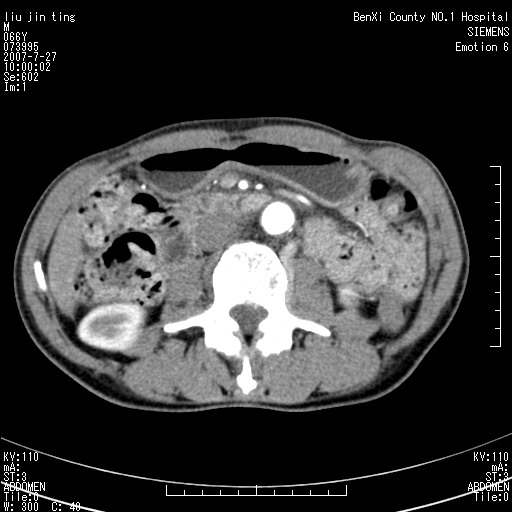

腹痛,背痛,无恶心呕吐,不黄,彩超示胰腺钩癌,ct扫描病灶平扫30-40hu,增强后动脉期40--60hu,静脉期50-68hu,真的是钩突上的么?您要试一试么?

动脉期

静脉期

沿着肠系膜上动脉呈匍匐性生长的软组织肿块,形态不规则,包绕肠系膜上动脉,呈明显强化,考虑来源于肠系膜的恶性肿瘤

沿着肠系膜上动脉呈匍匐性生长的软组织肿块,形态不规则,包绕肠系膜上动脉,呈轻-中度强化,考虑来源于肠系膜的恶性肿瘤。